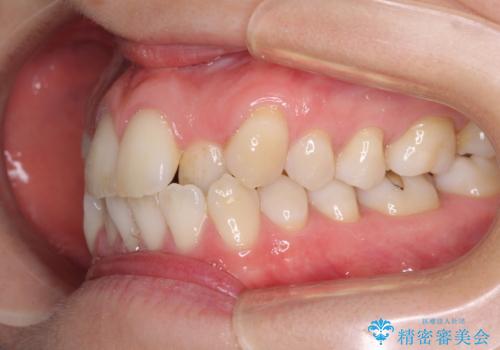

- 受け口傾向でクロスバイトの前歯を治したいとのことで来院された患者様です。

下顎骨が若干左側に変位していたため、右側にアンカースクリューを使用し、積極的に移動させながらインビザラインにて矯正治療を行うこととしました。

インビザラインによる矯正治療は、受け口傾向の治療に非常に適した方法であり、事前にシミュレーションに沿って治療を進めることできます。

今回の治療では骨格的な偏位があったためアンカースクリューを使用し、より確率の高い治療を行うことができました。